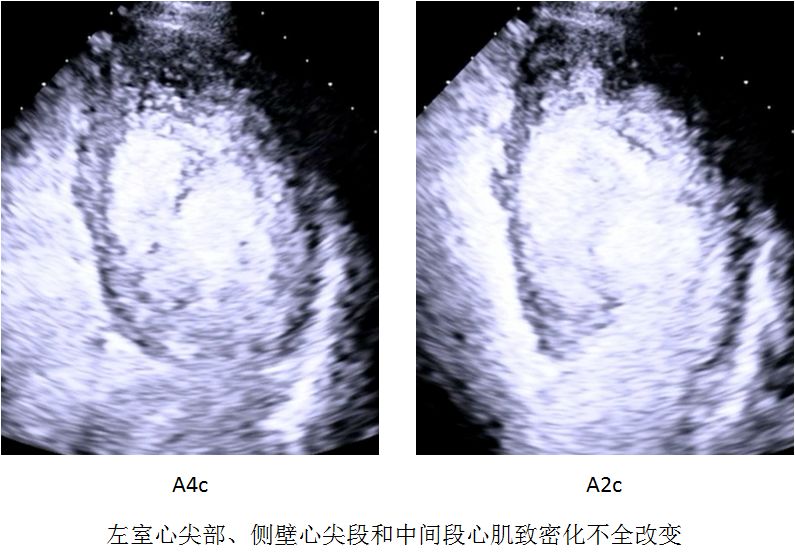

左心室壁增厚,包括2层:一层较薄的致密化心外膜层和一层显著增厚的非致密化心内膜层,内层有数目众多的突出小梁形成和深陷的小梁间隐窝,并且胸骨旁短轴切面上收缩末期非致密化心肌与致密化心肌(non-compacted to compacted, NC:C)的最大比值大于2:1

左心室下壁和侧壁的心尖段或中段有明显的小梁网状组织

▶▷ 2018年10月29日-31岁男性,心力衰竭入院